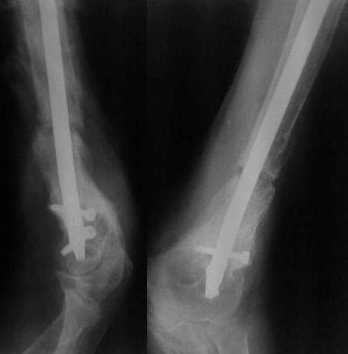

Неудачный остеосинтез пластиной: поломка винтов. После удаления сформирался гиполастический ложный сустав. Остеосинтез АВФ, циклическая компрессия-дистракция в области ложного сустава привела к формированию хорошей рентгенологической костной мозоли. Через 1,5 месяца ходил в аппарате без дополнительных средств опоры. Через 6 месяцев после клинической пробы - демотаж. Через 4 месяца после демонтажа - лизис костной мозоли, рецидив деформации.